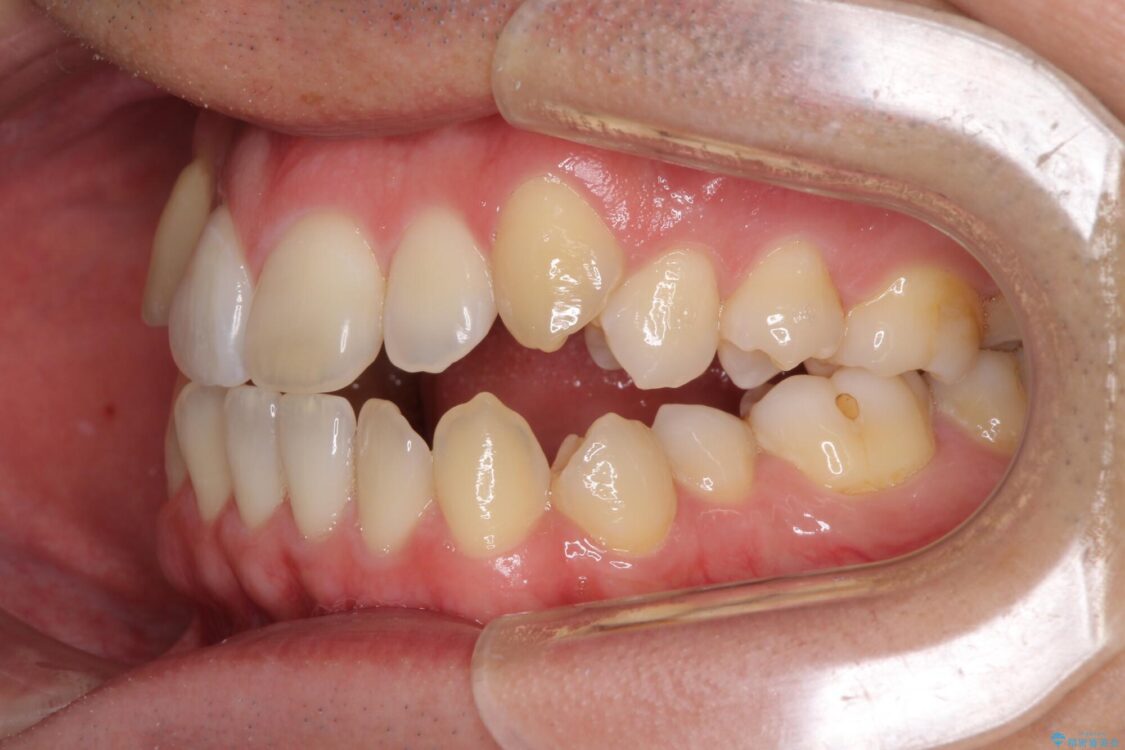

治療前

• 左右の八重歯が気になる ワイヤー装置での咬み合わせ改善 治療前画像